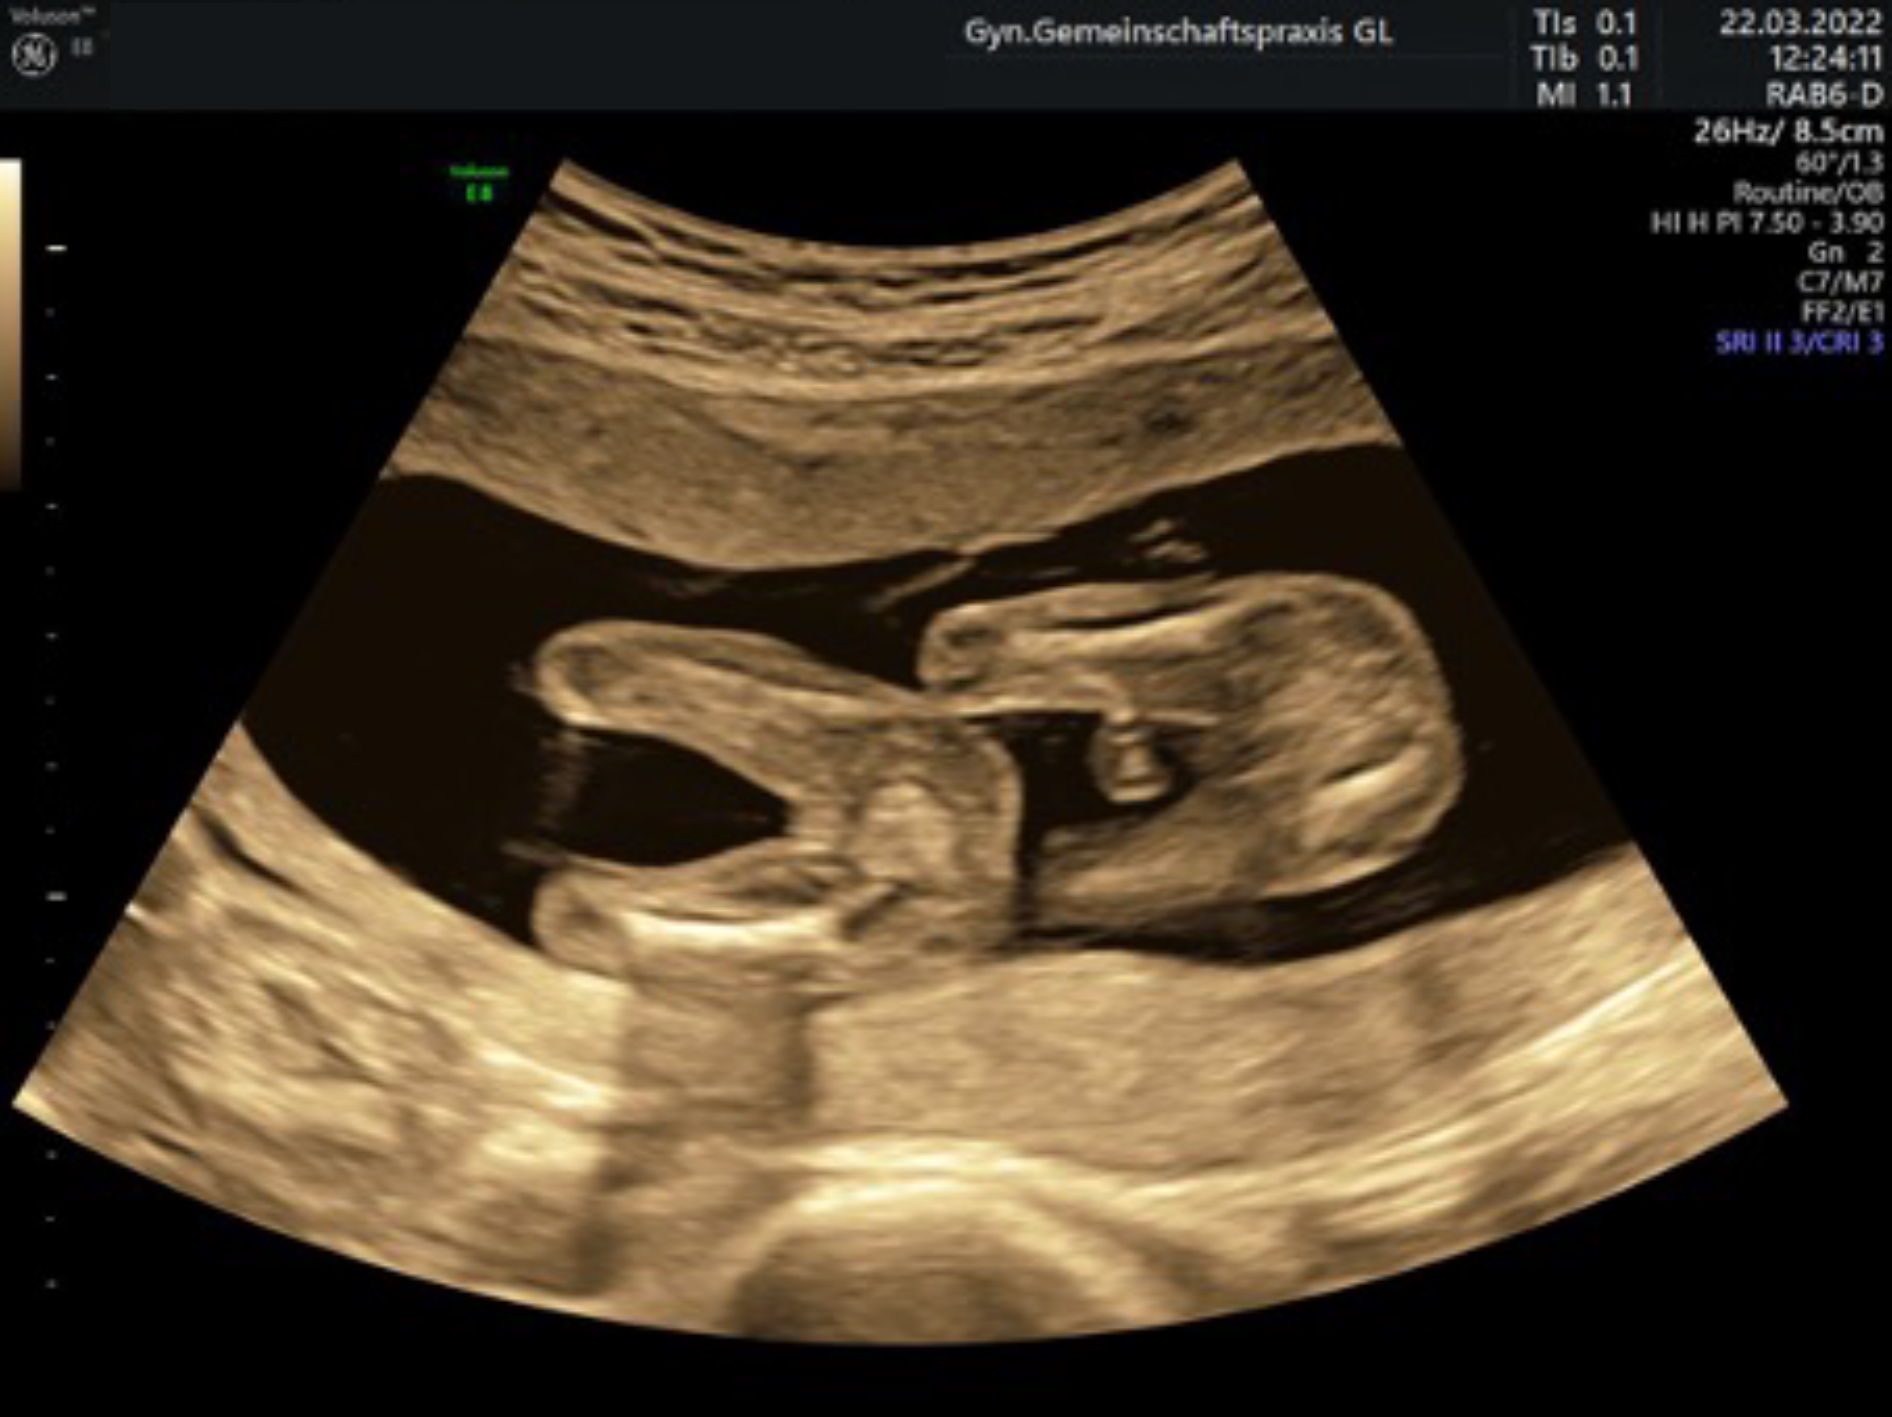

Ersttrimesterscreening mit individueller Risikoberechnung

(auch Nackentransparenzmessung/frühe Organdiagnostik genannt)

Zwischen der 12. und 14. Schwangerschaftswoche lagern die Kinder Flüssigkeit im Bereich des Nackens ein. Bei manchen Kindern ist dies verstärkt der Fall und kann dann zusammen mit Veränderungen bestimmter Blutwerte der Mutter einen Hinweis auf eine Chormosomenstörung (z. B. ein Down-Syndrom) geben.

In sehr großen Studien an über 100.000 Schwangerschaften wurden diese Messwerte mit der Risikoerhöhung für einen Chromosomenfehler des Kindes überprüft, die Vorhersagegenauigkeit ist deutlich besser, als die Abschätzung über das Alter der Mutter (bis ca 90%).

Zusammen mit einem ausführlichen Ultraschall (frühe Organdiagnostik) incl. des kindlichen Nasenbeins, der intakten Funktion einer Herzklappe und dem Blutfluss zwischen Mutter und Kind wird die Zuverlässigkeit der Risikoberechnung noch genauer und kann dann auch auf andere Fehlbildungen, z. B. einen Herzfehler oder einen offenen Rücken, hinweisen.